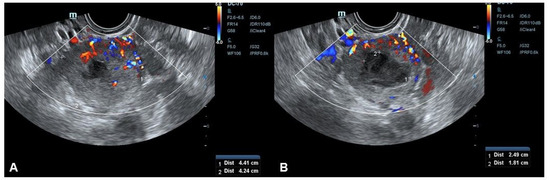

| Giannella, (the present report) | n = 1 | 4.7 × 3.3 × 4.5 | Heterogeneous | SS | Central rich vascularization | Intense central anechoic portion | Well-delimited borders | Smooth muscle tumors of uncertain malignant potential |